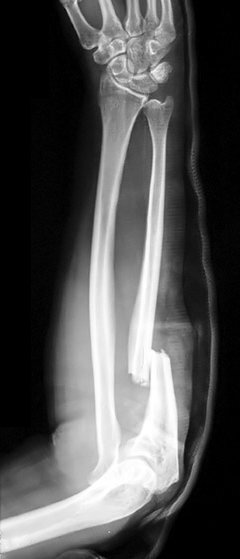

Fratura-luxação de Galeazzi

Fratura diafisária médio-distal do rádio, associada a lesão da articulação radioulnar distal.